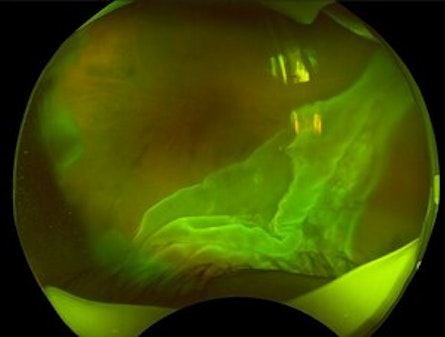

Total Rhegmatogenous retinal detachment with lattice degeneration & Vitreous haemorrhage

72-year male presented PVD induced total retinal detachment with vitreous hemorrhage.